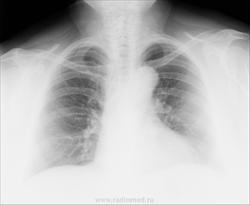

Женщина, 63года, жалобы на длительный кашель, общую слабость. Слева адгезивный плеврит? На боковом треугольная тень от корня? Помогите с диагнозом (рентгенолог будет только на следующей неделе).

Жидкости не вижу, слева спереди тень избыточной прекардиальной клетчатки. Эналаприл или его аналоги принимает?

Как-то не нахожу плеврита.

Увеличение левого желудочка, усиление дуги аорты, диффузное усиление легочного рисунка. Картина может соответствовать явлениям застоя в малом круге кровообращения.

А почему бы тени не быть плевральными спайками? Тоже похоже,.. значит, близко плеврит.)